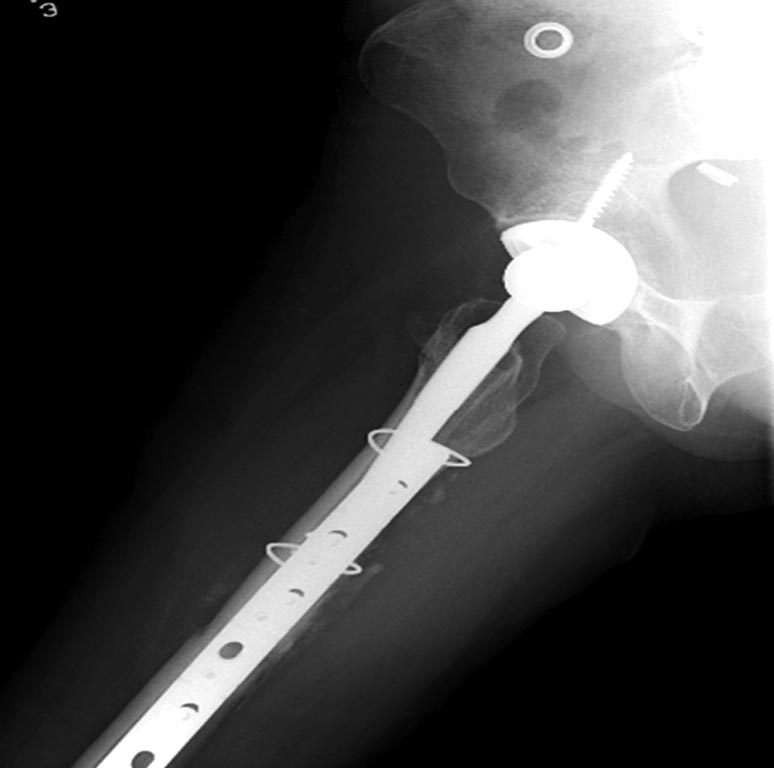

На 25 день с момента травмы операция на Jackson table с боковым обширным

доступом. Удаление стержней с местной обработкой. В тазобедренном

суставе удаление головки, на дне вертлужной впадины полная отслойка

хряща. Вертлужный компонент с одним винтом и короткая ножка -  Fitmore

Выписана. Нагрузку разрешили на левой стороне, а полная в 3 мес.  Здесь

снимки при амбулаторном наблюдении​: послеоперационно, 2 мес, 3 мес и 6

мес. Нагрузка полная, отсутствует хромота, и нет жалоб.